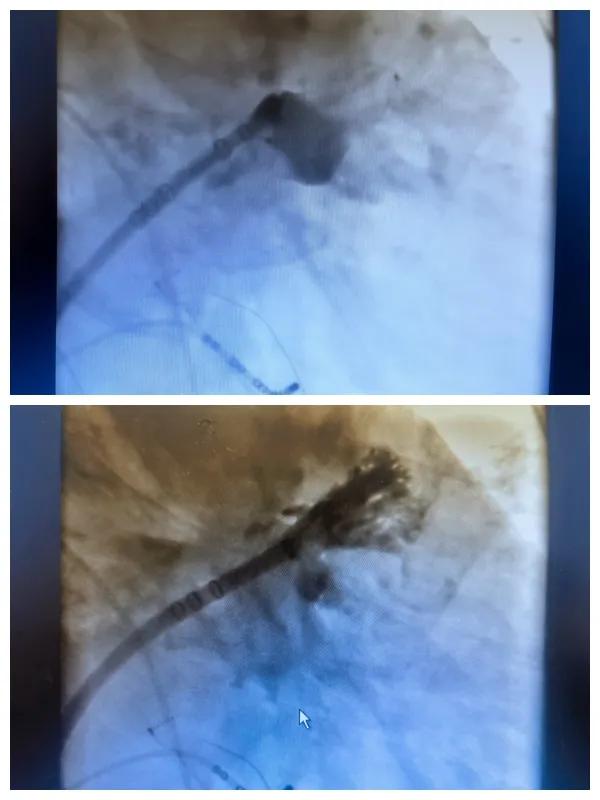

6月26日,市二院成功為一名老年房顫患者實(shí)施了房顫射頻消融術(shù)+左心耳封堵WM FLX一站式介入治療,標(biāo)志著醫(yī)院在心律失常介入治療領(lǐng)域邁出了嶄新的一步,開啟了新的治療篇章。

本次手術(shù)特邀我國著名心血管內(nèi)科專家、河南省胸科醫(yī)院黨委書記袁義強(qiáng)及血管內(nèi)科七病區(qū)主任黃瓊教授蒞臨指導(dǎo),市二院院長王瑾帶領(lǐng)心血管內(nèi)科電生理等專家團(tuán)隊(duì)緊密合作,一次性解決了患者房顫、血栓兩大困擾,也使患者告別了終身服用抗凝藥的痛苦,極大地降低了患者的經(jīng)濟(jì)和用藥負(fù)擔(dān)。

為了讓患者得到全面、綜合的治療,經(jīng)過團(tuán)隊(duì)術(shù)前充分討論,并征得家屬同意,心血管內(nèi)科團(tuán)隊(duì)決定采用目前國內(nèi)外先進(jìn)的房顫射頻消融術(shù)+左心耳封堵WM FLX一站式介入微創(chuàng)手術(shù)來治療老人的疾病。整個(gè)手術(shù)過程圓滿順利,術(shù)后何大爺各項(xiàng)體征正常,蘇醒后順利返回病房。